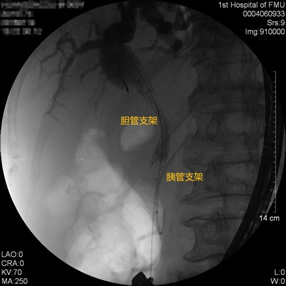

胃毕-Ⅱ术后乳头倒置 胃毕-Ⅱ术后胰管胆管双支架植入 胃毕-Ⅱ术后金属支架植入

胃毕-Ⅱ术后胰管胆管双支架植入 胃毕-Ⅱ术后胆管金属支架植入